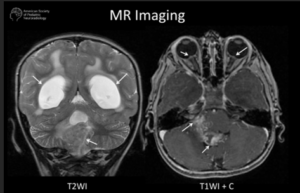

A 3-year-old child is admitted to the hospital due to decreased appetite and weight loss. She has been afebrile, and has not had vomiting or diarrhea.

Her activity level has decreased over the past two weeks.

She had been healthy until 2 months ago, when she was hospitalized for 48 ...

infection with mild respiratory distress and poor fluid intake.